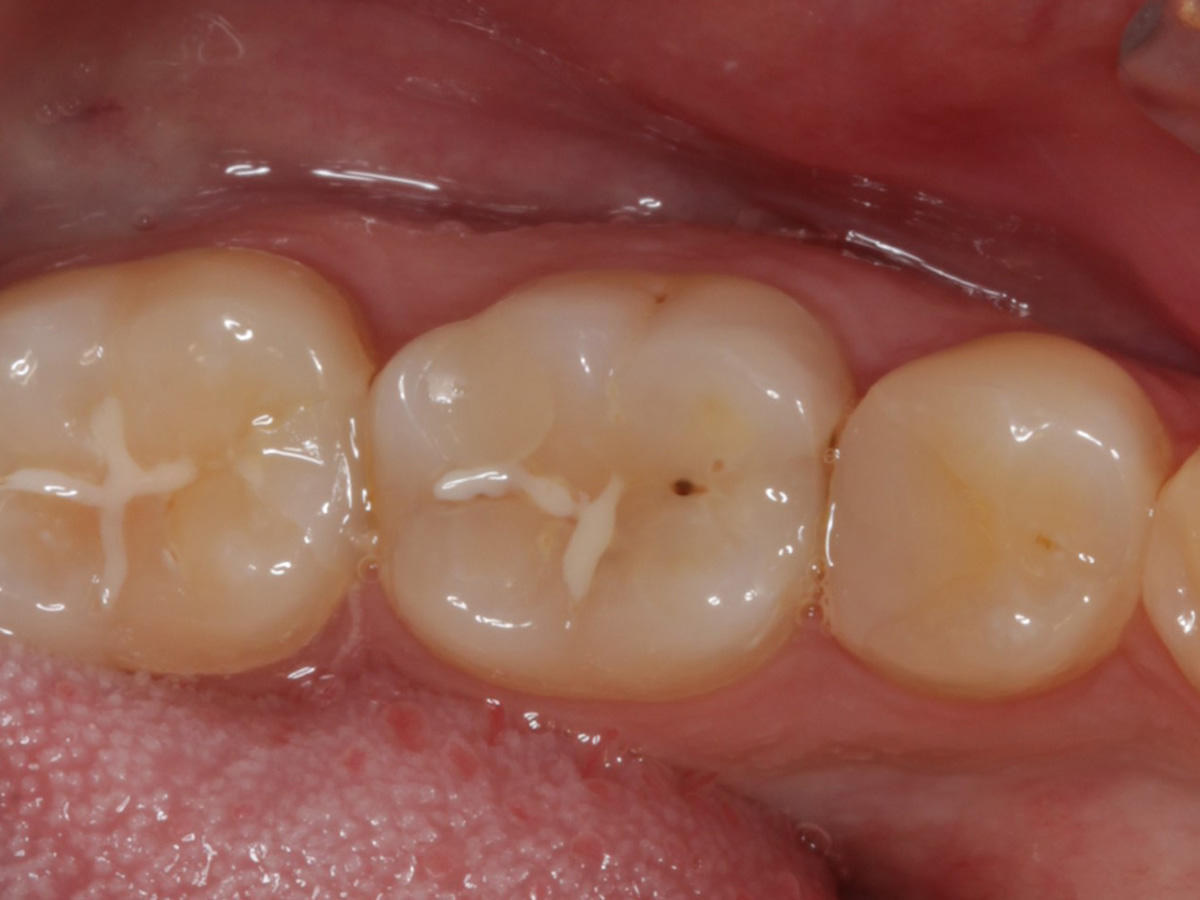

Abbildung 1

Intakte Kaufläche bei Approximalraumkaries an Zahn 36 mesial und distal